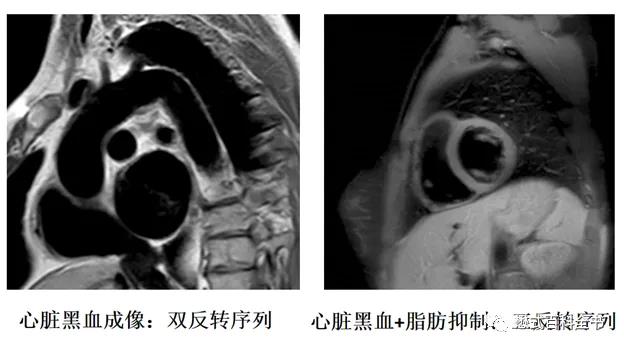

所谓的双反转黑血序列,就是在采集信号之前,首先施加了两个反转脉冲,将磁化矢量从纵向翻转到负方向。这个技术一般会和心电同步技术联用。当检测到QRS波时,首先施加第一个反转脉冲,这个反转脉冲是非层面选择的180°脉冲,将所有组织的磁化矢量都反转到-Z。接着一瞬间立马施加第二个反转脉冲,这个反转脉冲是层面选择的180°反转脉冲,只有被选择的层面反转180°,等于返回原来状态。也就是说,通过连续两个反转脉冲,成像层面的组织磁化矢量是在正方向,而成像层面以外的所有组织磁化矢量是在负方向。被反转到负方向的组织会进行纵向驰豫,逐渐向正方向恢复。当血液组织的磁化矢量刚好过零点时,这个时间施加90°射频脉冲,则血液组织信号被抑制,也就是层面外的所有血液组织信号被抑制掉。而层面内的血液由于信号流空也不会产生信号,并且层面外血液信号被抑制,即使流入采集层面也不产生信号,所以整个血液信号被抑制。

这种序列其实就是在快速自旋回波序列之前施加了连续两个反转脉冲,两个反转脉冲可以看作是为了形成黑血效果而做的准备脉冲阶段,而后面的快速自旋回波则是信号采集阶段。有了这个双反转脉冲,就可以保证无论是层面内,还是层面间的血液信号都被抑制。即使有血液在这个过程中,流出再流入采集层面,也不胡产生信号,保证了黑血效果的稳定性。

双反转BB序列一般都是2D成像序列,所以其实这个序列抑制血液的效率不高。因为每次抑制一层,都会进行双反转脉冲发射,如果扫描层数多了,扫描时间也会成倍的增加。